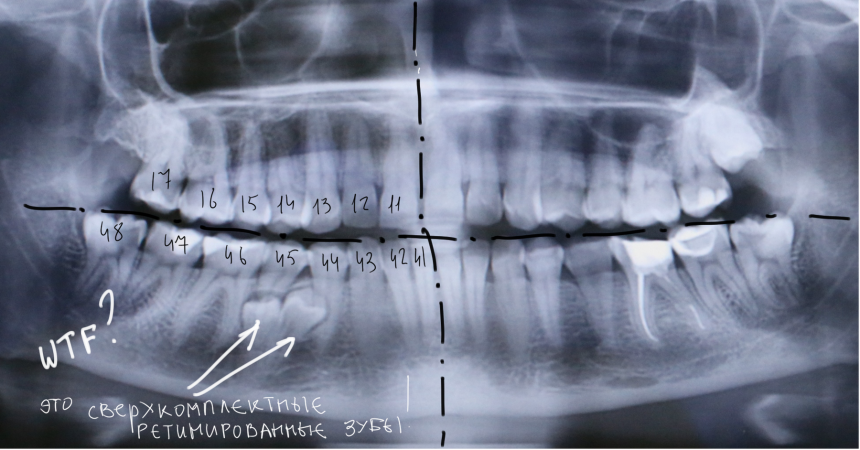

Вот разбор снимка:

Давайте еще раз посмотрим на снимок:

Что мы на нем видим? Ну да, есть два лишних зуба.